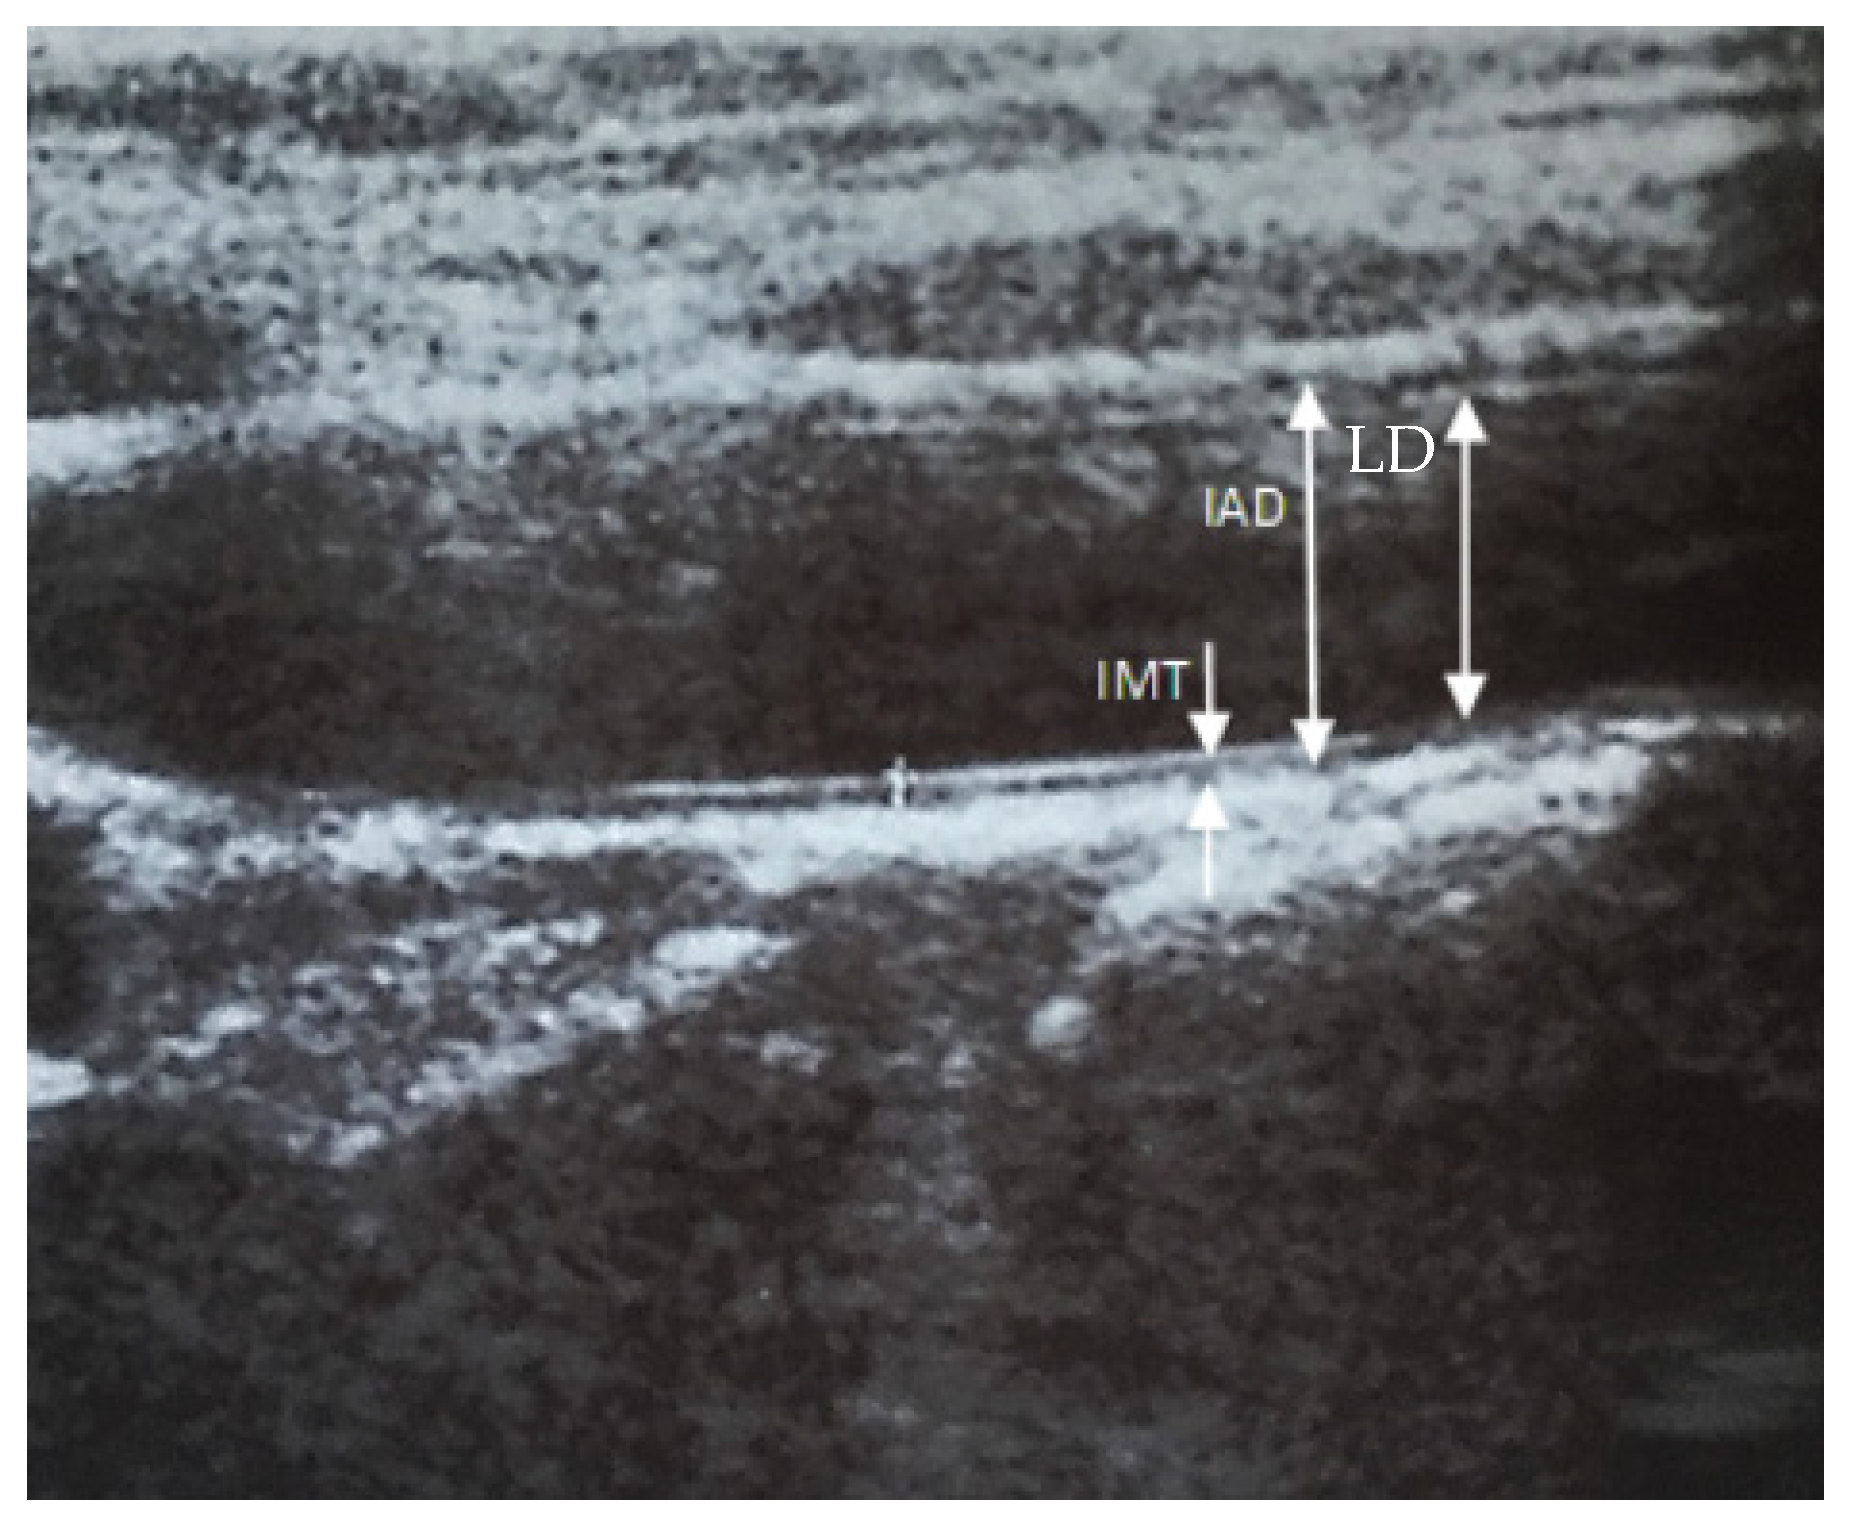

An Intima media thickness (IMT) measurement of the distal segment of the carotid arteries was performed by ultrasound using an Acuson Antares 10 Mhz linear head in B-mode. In order to ensure the best repeatability of the results, the tests were carried out by only one person—an experienced ultrasonography specialist. The thickness of the IMT complex was defined as the distance between two clearly shining distal wall lines. The first is the border between the lumen of the vessel and the inner membrane, the second sets the border between the middle membrane and the adventitia (Figure 1). IMT complex thickness measurements were made at several points (minimum 3) within the distal wall, about 1 cm proximal from the common carotid sinus (bifurcation for the internal and external carotid artery). The mean of all the measurements was taken as the result [12,13]. All activities were then repeated by conducting the study on the opposite side.

Figure 1. Diagram of the common carotid artery in ultrasound examination. IMT—intima media thickness, IAD—interadventitial diameter; LD—lumen diameter.